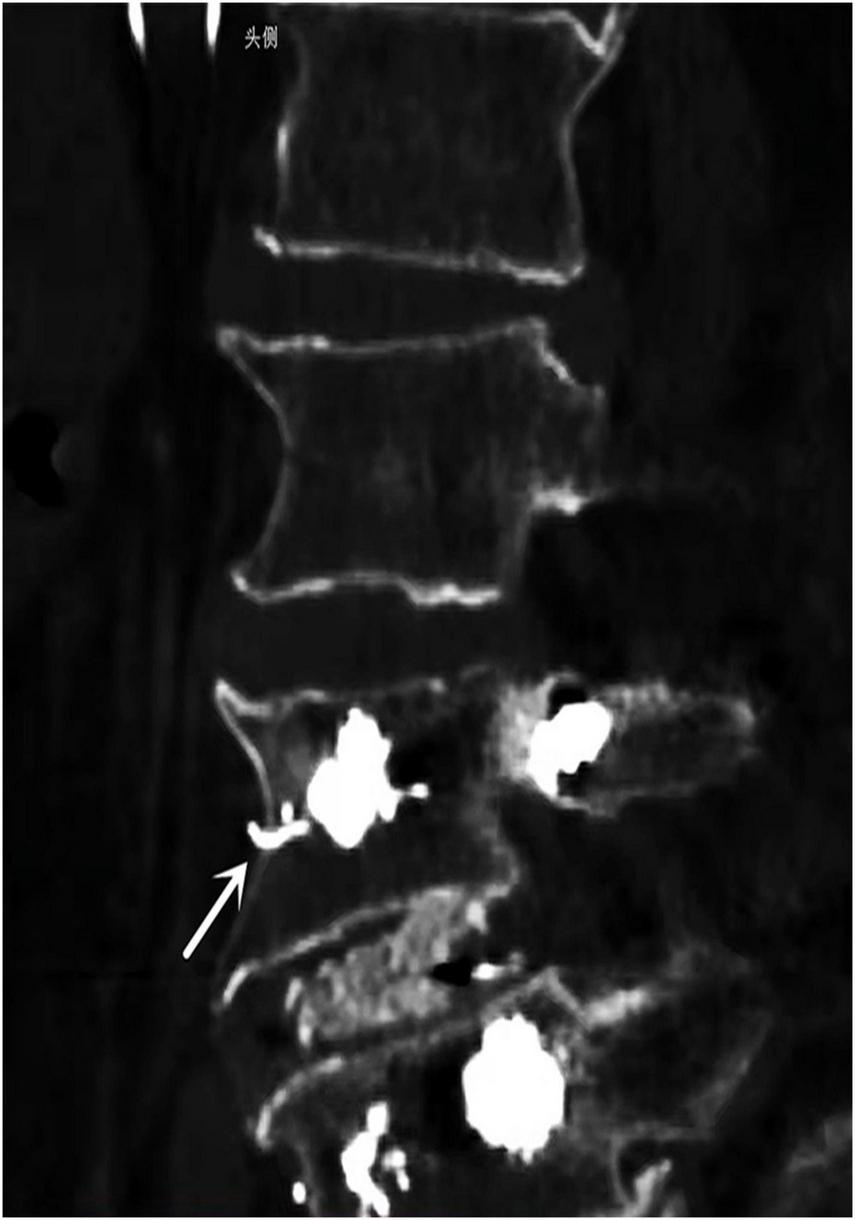

Thereafter, X-ray examination showed paravertebral venous cement leak and cement entry into the IVC, resulting in the deposition of a cement cast in the IVC filter, and CT images demonstrating cement leaking out of the vertebral body (Figure 1). An inferior vena cavography prior to retrieval of the filter showed that cement had migrated into the IVC and attached to the caval wall at the level of the IVC filter tip and was trapped within the filter (Figure 2), resulting in the IVC filter failing to be retrieved in the conventional way.

FIGURE 1

CT scans revealed strip-like high density cement extravasation (arrows) in vertebra bone.